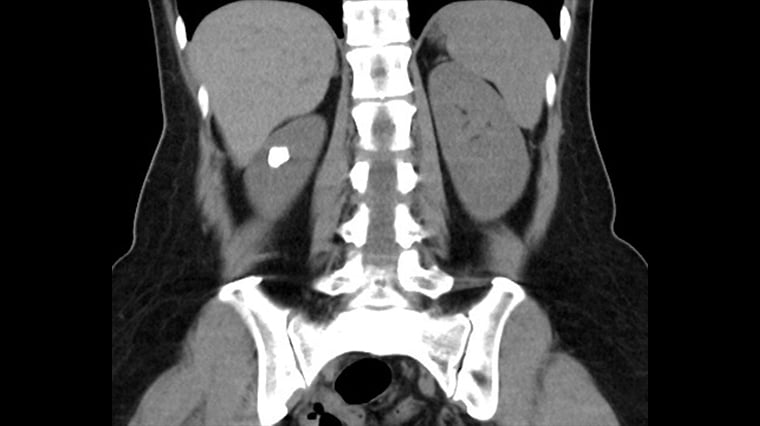

鐘伯恩指出,個案在接受電腦斷層檢查後發現,其左側腎臟內約有1.5cm的結石群嵌在腎盞憩室中,而憩室與正常腎盞之間的通道僅不到1mm,導致尿液排出不良並形成結石。手術先以具止血效果的雷射切開並擴大憩室狹窄通道,接著以「負壓吸引鞘與軟式輸尿管鏡碎石手術」將結石擊碎並同步吸出,最後放置雙J導管維持通道通暢,直至傷口定型後再行取出,藉此降低日後再次狹窄及尿液滯留的風險。術後個案恢復良好,隔日即順利出院,成功解決多年來的結石與反覆感染問題。